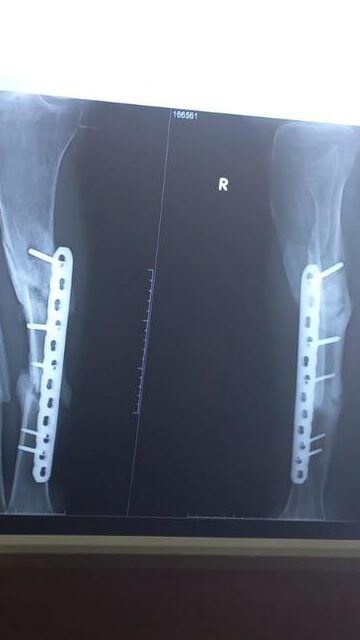

Bədənim dəfələrlə qırıldı,

çanağıma, çənəmə protezlər qoyuldu,

ayağıma millər yerləşdirildi…